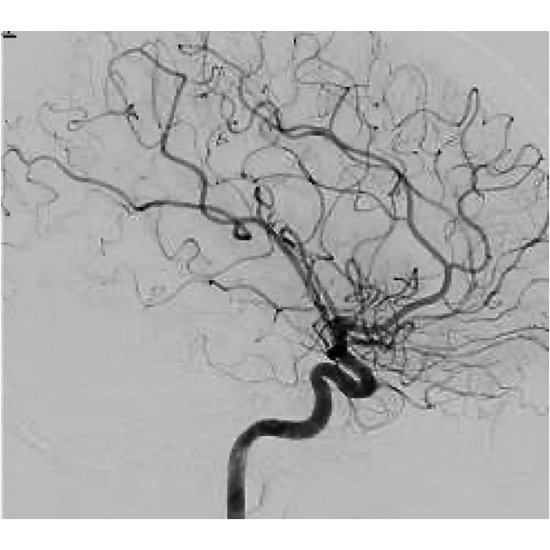

Cerebral Angiogram 9/2023: occlusion of right Middle Cerebral Artery and Anterior Cerebral Artery